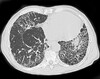

What pathology is seen here?

Bronchiectasis ## Footnote -Seeing cysts (advanced) -Fibrosis throughout the lungs

108

Bronchiectasis ## Footnote -Airway very dilated -Walls are normal thickness

109

Bronchiectasis ## Footnote -Signet ring appearance (ring is the bronchus, stone sitting on the ring is the blood vessel beside)

110

Bronchiectasis ## Footnote -Large airways -Collection of mucus in airways

111

Bronchiectasis; String of pearls